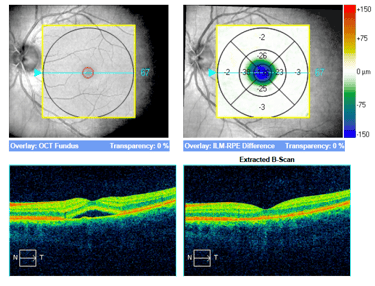

Trzy przykłady SML z dobrym efektem terapeutycznym wykonanej w długotrwałej postaci CSCR.